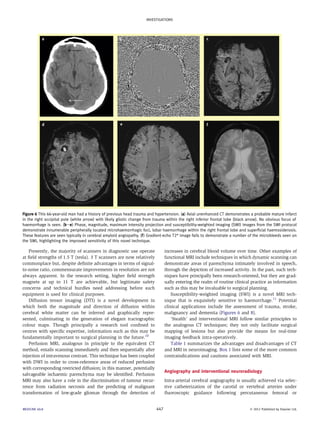

Figure 6 This 66-year-old man had a history of previous head trauma and hypertension. (a) Axial unenhanced CT demonstrates a probable mature infarct

in the right occipital pole (white arrow) with likely gliotic change from trauma within the right inferior frontal lobe (black arrow). No obvious focus of

haemorrhage is seen. (bee) Phase, magnitude, maximum intensity projection and susceptibility-weighted imaging (SWI) images from the SWI protocol

demonstrate innumerable peripherally located microhaemorrhagic foci, lobar haemorrhage within the right frontal lobe and superficial haemosiderosis.

These features are seen typically in cerebral amyloid angiopathy. (f ) Gradient-echo T2* image fails to demonstrate a number of the microbleeds seen on

the SWI, highlighting the improved sensitivity of this novel technique.

Susceptibility-weighted imaging (SWI) is a novel MRI tech-nique

that is exquisitely sensitive to haemorrhage.11 Potential

clinical applications include the assessment of trauma, stroke,

malignancy and dementia (Figures 6 and 8).